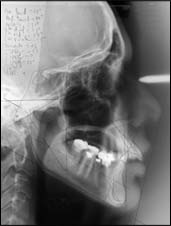

Si un traitement orthodontique est envisagé, l’orthodontiste va prescrire ou effectuer des examens complémentaires (radiographies, moulages en plâtre, photographies), faire un bilan clinique précis (avec des mesures et des constructions) pour proposer un plan de traitement adapté au patient.